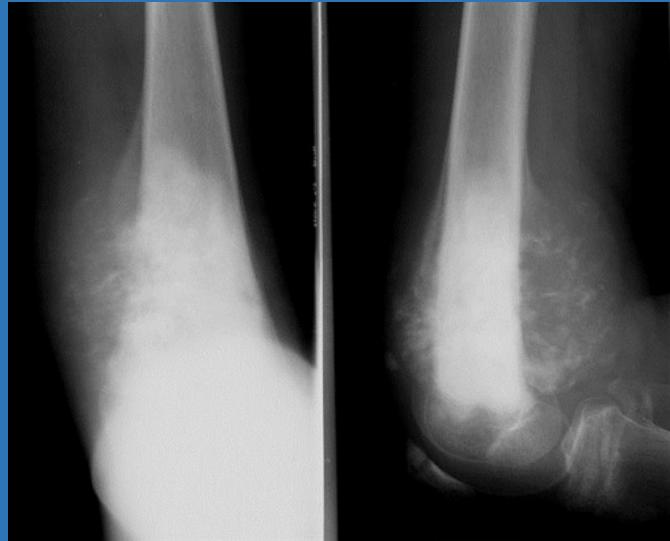

Case 1: Pediatric Elbow Infection (6 years old)

Clinical Presentation

- Localized tenderness

- Hotness and local redness

- Swelling and edema

- Reduced range of motion of the elbow

Differential Diagnosis

- Osteomyelitis

- Cellulitis

- Septic arthritis

- Both septic arthritis and osteomyelitis (can occur simultaneously, especially proximal femur and hip)

- Ewing sarcoma

Laboratory Investigations

- Complete Blood Count (CBC): Leukocytosis with neutrophilia

- C-reactive protein (CRP): Raises very early in infection

- Erythrocyte Sedimentation Rate (ESR): Raises several days later

- Blood culture: Identify causative organism

- Aspiration from sub-periosteal collection or joint:

- Gram stain

- Culture and sensitivity testing

Aspiration Fluid Analysis

- Clear colorless: Normal

- Clear yellow (can read through): Non-inflammatory

- Turbid: Inflammatory

- Pus: Bacterial infection

- Blood: Hemorrhagic or traumatic tap

Imaging Studies

- X-ray: First signs appear at 10-14 days

- Metaphyseal rarefaction

- Periosteal reaction (new bone formation)

- Bone Scan: Detects early signs of infection

- MRI: Shows area of affection (joint vs. metaphysis vs. both)

Note: MRI is perfect for detecting early signs of infection, replacing bone scan in many cases.

Treatment Protocol

- Supportive treatment: Pain management and hydration

- Splint immobilization: To prevent further damage

- Antibiotic therapy:

- I.V. flucloxacillin (must start early after aspiration)

- Consult microbiologist for optimal antibiotic selection

- Modify based on culture and sensitivity results

- Surgical intervention: Debridement and drainage as needed